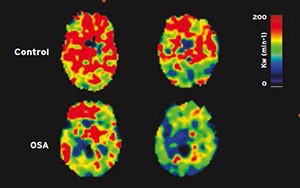

Obstructive Sleep Apnea (OSA)

Brain maps showing compromised blood-brain barrier function in one person with OSA (left) and one person with a healthy brain. Regions with yellow-to-red areas represent an intact blood-brain barrier; regions with blue-scale colors indicate an altered blood-brain barrier.

Obstructive sleep apnea contributes to a breakdown of the blood-brain barrier that plays an important role in protecting brain tissue by limiting harmful bacteria, infections, and chemicals from reaching the brain.

Studies have found that a compromised function of the blood-brain barrier is associated with significant brain damage in stroke, epilepsy, meningitis, multiple sclerosis, Alzheimer’s disease, and other conditions. Blood-brain barrier becomes more permeable in obstructive sleep apnea, a breakdown that could contribute to brain injury, as well as potentially enhancing or accelerating the damage. This type of brain injury in obstructive sleep apnea has significant consequences to memory, mood, and cardiovascular risk, but physicians and researchers have developed pharmacologic and non-pharmacologic therapeutic strategies to repair blood-brain barrier function in other conditions.